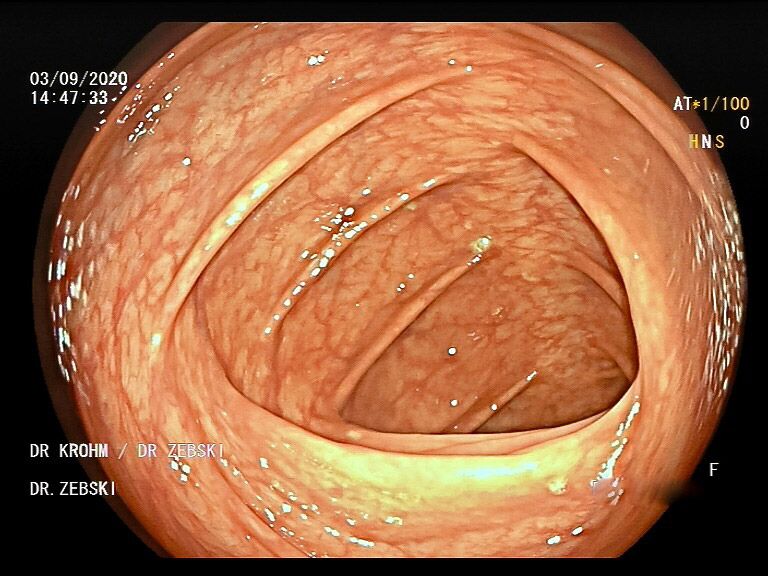

Die Darmspiegelung ist der uneingeschränkte Goldstandard für die Diagnostik und Vorsorge sämtlicher Erkrankungen des Dickdarms und des untersten Dünndarms. Die hochauflösende Bildqualität (High Definition) unserer modernen Videokoloskope ermöglicht eine zuverlässige Einordnung nahezu sämtlicher entzündlicher oder geschwulstiger Veränderungen der Dickdarmschleimhaut.

Die Darmspiegelung hilft, dass Darmkrebs gar nicht erst entstehen kann. Denn während der Untersuchung werden auch Polypen entfernt, aus denen sich der Darmkrebs in der Regel entwickelt. Von allen Maßnahmen zur Früherkennung dieser Polypen besitzt die Koloskopie die höchste Empfindlichkeit. Sie weist kleinste Polypen, aber auch Darmkrebs nach, der noch keinerlei Symptome macht. Die Abtragung dieser Polypen erfolgt direkt, wenn sie entdeckt werden. Das geschieht völlig schmerzfrei. Durch die Abtragung der Polypen kann die Entstehung von Darmkrebs effektiv verhindert und die krebsbedingte Sterblichkeit gesenkt werden.